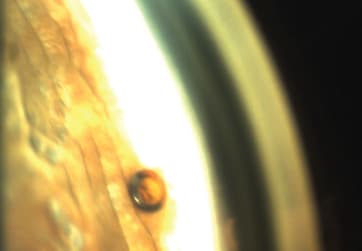

I place the inserter with the CyPass Micro-Stent loaded through the clear cornea incision, into the anterior chamber and lead it to the opposite side toward the angle. A small guidewire positions the device and gently separates the iris from the scleral spur to facilitate insertion (Figure 2). At first I establish contact of the tip with the scleral spur. After I feel resistance, I place the tip under the scleral spur and slowly advance the micro-stent into the small cleft the guidewire creates, and release it at the desired depth, leaving only the proximal collar of the device in the anterior chamber.

Figure 2. CyPass Micro-Stent on the delivery guidewire just before separation of the iris from the scleral spur.